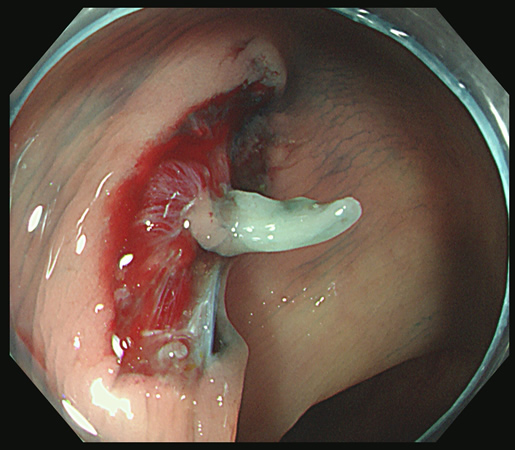

切除創に白い突起(CSDP)があり、よく見ると根本に粘膜の遺残が見られます

切除創を時間をかけて丁寧に観察することが重要です

これをカンシで大きくつかみ取ります